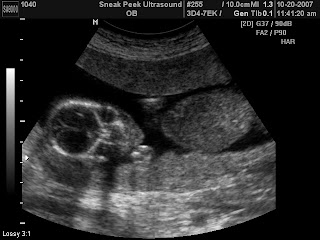

IT'S A...

Girl!!!

We recently learned that we are blessed to again be expecting another little girl. Chris, Eliana and I all expected it, but it's still weird to actually know. Now we're really going to be put under pressure to decide on a name! Eliana's been asking for weeks, "What is her name?" and we would tell her that we couldn't name the baby until we knew whether it was a boy or a girl. She would always respond, "Mom, it's a girl!" When we told Eliana that she was right she looked at us like, "What? You guys didn't know?" Honestly though, she has a good track record for these things. I really should start charging for her services.

So...three girls. Wow. God has not only hand-picked her for our family, He has handmade her. I had ultrasounds with my other two girls, but it never ceases to amaze me to see a unique individual with fingers and toes moving inside me. I can hardly believe that the Lord has so graciously blessed our family with this new, precious daughter. Please join us in praying for her (and for us!).